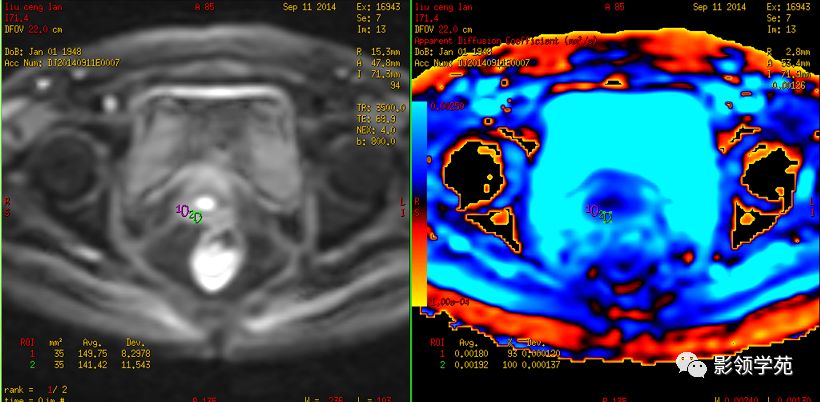

磁共振扩散加权成像,DWI

DWI是目前唯一能在活体观察组织水分子微观运动的无创性影像学方法,可以检测出与组织含水量变化相关的形态学和生理学早期改变,并以表观扩散系数(ADC)值来量化表示。

DWI在宫颈癌中的应用

DWI:局限性高信号,癌组织ADC值<癌旁组织<小于正常宫颈组织

DWI显示淋巴结肿大